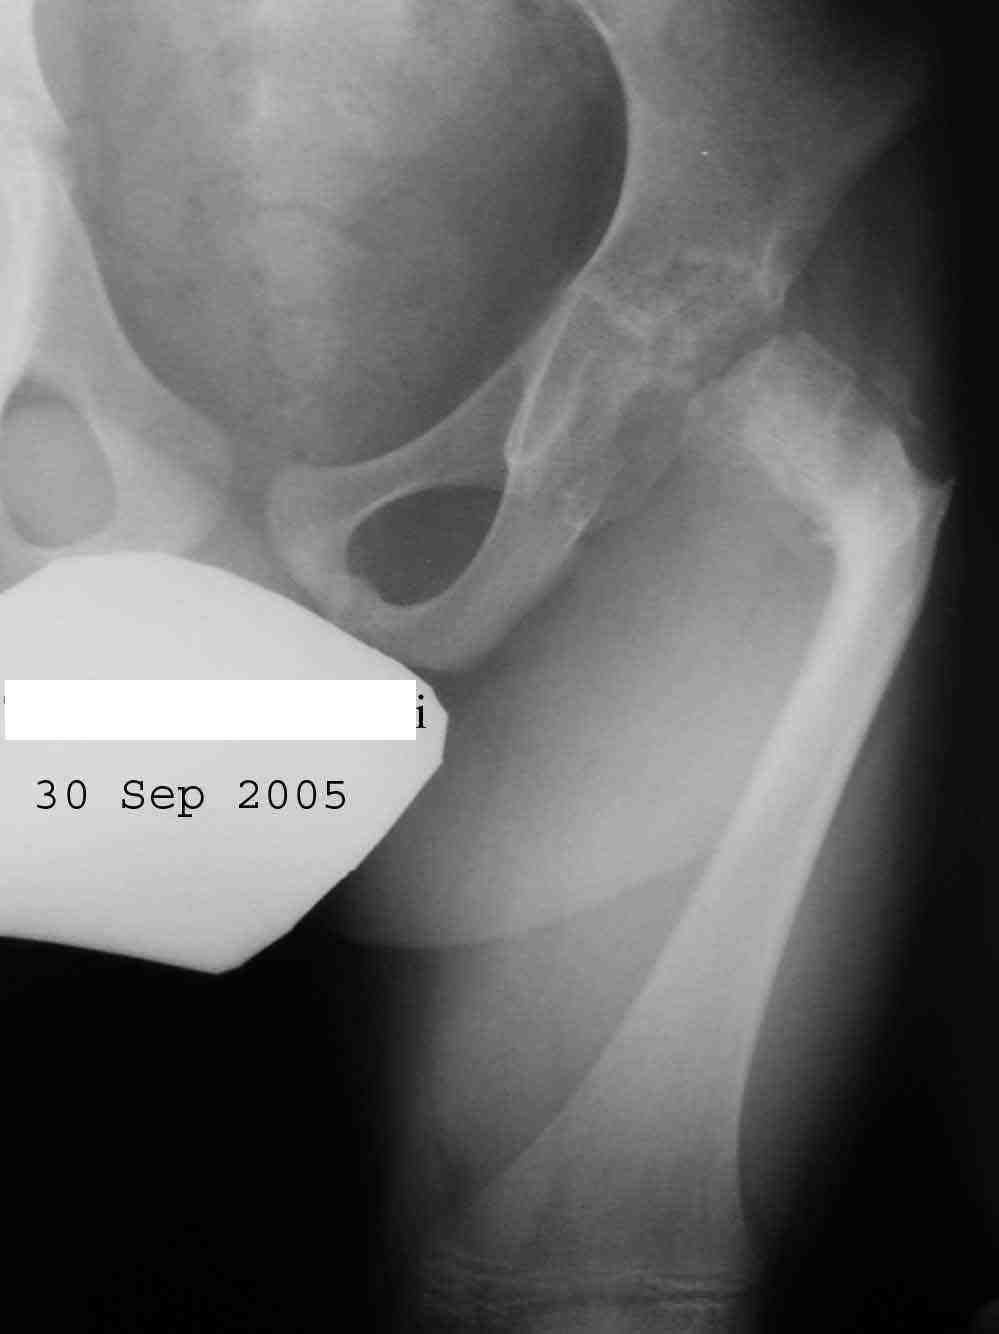

Извините за задержку(по техническим обстоятельствам) еще просим извинения за ошибки (трудный перевод). Больной с врожденной гипоплазией проксимальной части бедра, с ацетабулярной дисплазией. В 6 лет первая операция по стабилизации тазобедренного сустава прилагаю Рг. К нам обратился в следующей ситуацией:укорочение на 26см нижней конечности, соха flecta - 45 °.подвижной до 100°, genu flexum 25-30° мобильный до 90°. Активность мышц бедра- очень слабое, мышцы голени и сама голень отстающей в развитии. В настоящее время пациент ходит самостоятельно с протезом. Спасибо всем еще раз за присланные варианты лечения.Rx при рождении:ниже